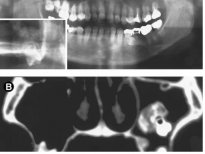

Diş yapısı en dıştan içe doğru mine (kök kısmında sement), dentin, pulpa olarak sıralayabiliriz. Mine, sement ve dentin hidroksiapatit kristalleri dediğimiz kalsifiye yapıdan oluşur ve büyük ölçüde kemiğe benzer. Hidroksiapatit kristalleri dişlere sertliğini verir ve dişlerin molekül yapısında eser miktarda su bulunduğundan dolayı oldukça serttir ve böylece çok büyük çiğneme kuvvetlerine dayanabilirler. Mine, vücuttaki en sert maddedir; öyle ki kemikten bile daha serttir. Bu kadar yoğun kalsifiye yapıların yumuşak dokuda gelişmeleri oldukça zor ve nadir olmasına rağmen çarpıcı örnekleri vardır.